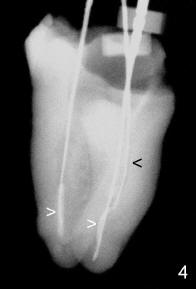

Fifty-four-year-old lady has a three-unit FPD involving #30-32 for 20 years. An acute infection develops in #32 abutment tooth with periapical radiolucency (Fig.1 *). Mesial and distal root canal fillings are short (black <). The pulpal chamber is not filled (white >). At higher magnification, the mesial margin is open. Additionally, the tooth #1 is missing. It appears that the tooth #32 has guarded prognosis. Treatment plan is to extract #32 and place an implant at #31.